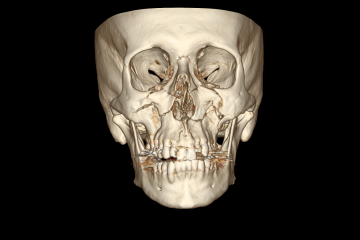

O maxilar quebrou em várias partes em ambos os lados da face. A parte da arcada dentária se soltou do crânio, ela recuou 7mm. Era visível a deformação, dava para sentir ela se acomodar quando eu falava.

Fiquei internado uma semana, a cirurgia para fixação dos ossos foi realizada com sucesso.

Essas são imagens da minha tomografia.